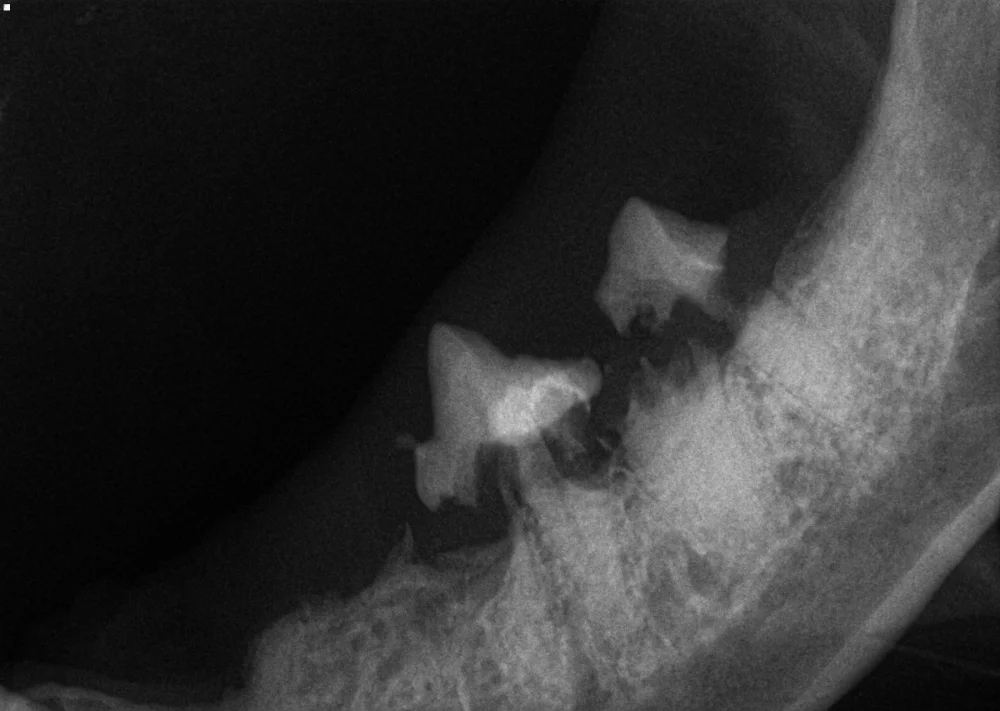

dental imaging of severe tooth resorption

A thorough, anesthetized oral exam is almost always necessary to diagnose TR in cats unless the lesions are so advanced (and painful) that the teeth eventually fracture or the crowns become “missing” in response to this inflammatory process. A veterinarian must probe each tooth, particularly along the gum line. However, TR most commonly takes place at the roots of the teeth. This means that TR occurs on the part of the tooth that exists below the gingiva (gum tissue), thus it can not be appreciated without dental imaging. This is why every cat who receives professional dental treatment should always undergo full-mouth dental imaging. Without interpreting the anesthetized oral exam and dental imaging together, TR can easily be missed, even by the most skilled veterinarians. Full-mouth dental imaging is accomplished by either dental radiography (x-rays), or even better, cone beam CT.